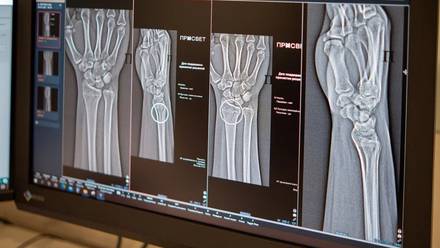

В Москве запустили два новых ИИ-сервиса для высокоточной диагностики множественных переломов голеностопного и лучезапястного суставов. Общее число разных по функционалу ИИ-сервисов для рентгенологов достигло 60. Об этом сообщила заместитель мэра Москвы по вопросам социального развития Анастасия Ракова.

— Цифровые решения уже более пяти лет помогают столичным рентгенологам — прежде всего в анализе медицинских снимков. Недавно мы запустили два новых ИИ-сервиса, которые помогают обнаруживать на рентгеновских изображениях травмы костей голеностопного и лучезапястного суставов — одних из самых функциональных и при этом уязвимых. Алгоритмы автоматически отметят поврежденные участки и выполнят необходимые измерения, даже если на снимке присутствуют признаки сразу нескольких переломов, — рассказала Анастасия Ракова.

Основными признаками перелома являются отек и боль, усиливающаяся при движении. Для сохранения мобильности суставов и минимизации негативных последствий необходима быстрая и точная диагностика с оценкой масштабов травмы.

ИИ-технологии в лучевой диагностике анализируют снимки по множеству параметров, помогают выполнять необходимые расчеты и ускоряют описание изображений. Они способны выявлять даже самые мелкие трещины и указывать врачу на наличие нескольких переломов в одной области. Корректная диагностика напрямую влияет на выбор тактики успешного лечения.